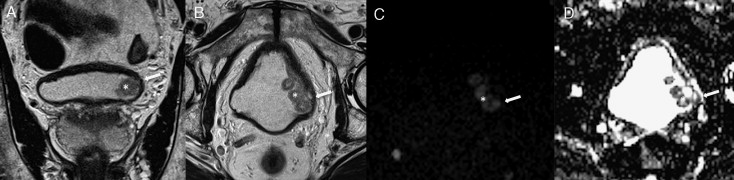

Figura 1. Exemplo de um tumor vesical localizado na parede lateral esquerda (*). A‐ T2 coronal B‐ T2 axial C‐ DWI (b1200) D‐ mapa ADC Nas sequências T2 observamos tumor vegetante, de sinal intermédio implantado na parede lateral esquerda da bexiga, que infiltra profundamente a parede vesical, condicionando descontinuidade focal da linha de hipossinal característica da muscularis própria, traduzindo tumor músculo‐invasivo. Estes achados são corroborados pelo estudo funcional de difusão, documentando‐se tumor com hipersinal em DWI e hipossinal no mapa ADC (setas). |